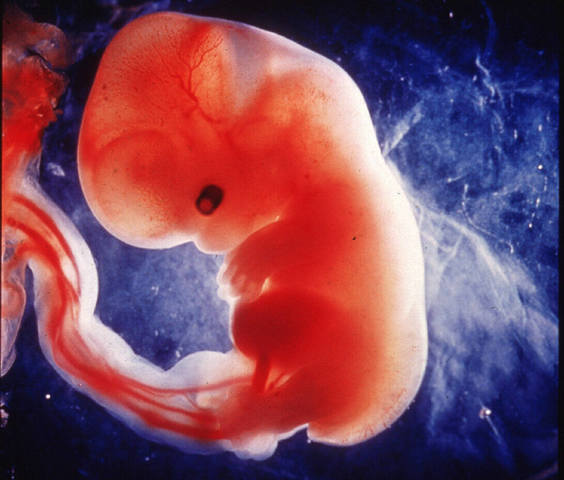

• El progreso de la embriología

El progreso de la embriología

Se dio impulso al progreso la Embriología. Se inventaron los diversos "seopios" estetoscopio, otoscopio, oftalmoscopio, laringoscopio, gastroscopio, cistoscopio, broncoscopio, estos instrumentos ampliaron el estudio de la Anatomía en el ser vivo.